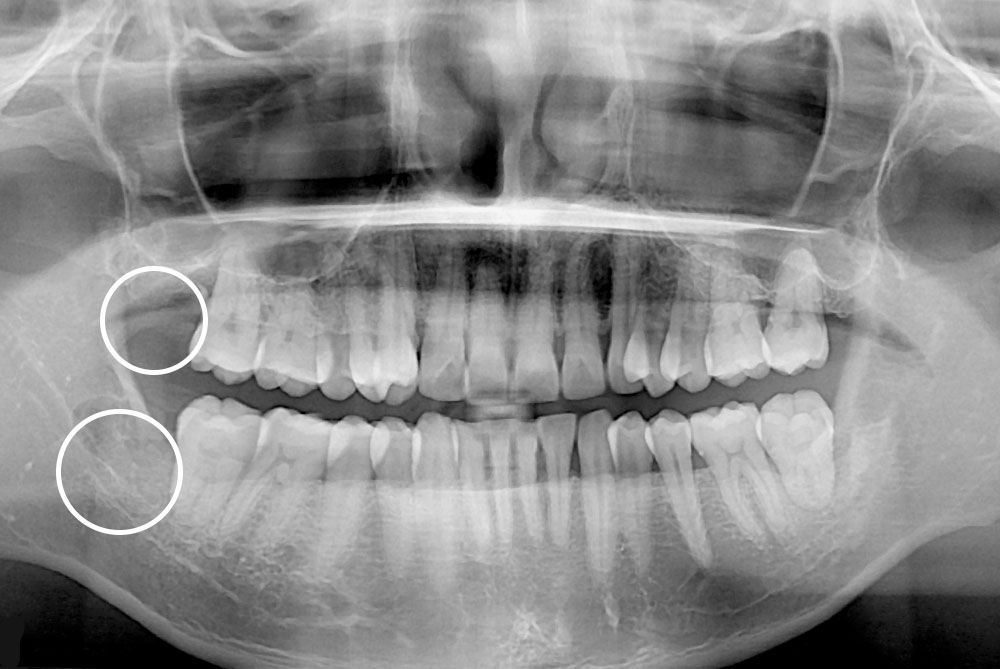

[사랑니] 매복 사랑니 발치

치료후 : 2019-05-14

세종치과는 구강악안면외과학 박사이신 원장님이 발치하는 치과입니다.